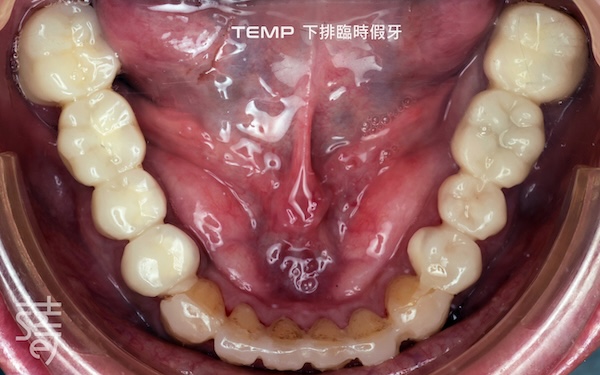

🔼 蒔美引進 DSD 微笑設計系統,讓患者在假牙製作前預覽未來笑容樣貌。再由數位牙體技術師同步製作臨時假牙,讓患者在實際試戴過程中,提前感受理想笑容的美觀與舒適,並根據李先生主觀感受進行微調,找到最終的完美方案。

Smile Introduces the DSD Smile Design System, Letting Patients Preview Their Future Smile. Digital dental technicians then create temporary prosthetics, allowing patients to trial their ideal smile and comfort. Adjustments are made based on Mr. Li’s feedback to achieve the final, perfected result.

陳教授特別重視「臨時假牙」的調整過程,逐一檢查每個咬點與滑動路徑,確保咬合力量平均分布、上下牙接觸自然順暢。這些微小修正,其實是預防顳顎疼痛、臉部肌肉緊繃、咀嚼困難或發音不清的關鍵。

Dr. Chen focused on fine-tuning the temporary prosthetics, checking each contact point and sliding path to ensure even bite force and smooth upper-lower tooth contact. These tiny adjustments prevent jaw pain, muscle tension, chewing difficulty, and speech issues.

為了達到極致精準,陳教授並未使用一般常見的咬合紙,而是採用僅 8 微米厚的 shim stock,能偵測出極細微的不平衡。對患者而言,看似細瑣的步驟,換來的卻是更自然、穩定且長久舒適的假牙體驗。

For maximum precision, Dr. Chen used an 8-micron shim stock instead of standard bite paper to detect the slightest imbalances. To the patient, these meticulous steps translate into prosthetics that feel natural, stable, and comfortable for the long term.